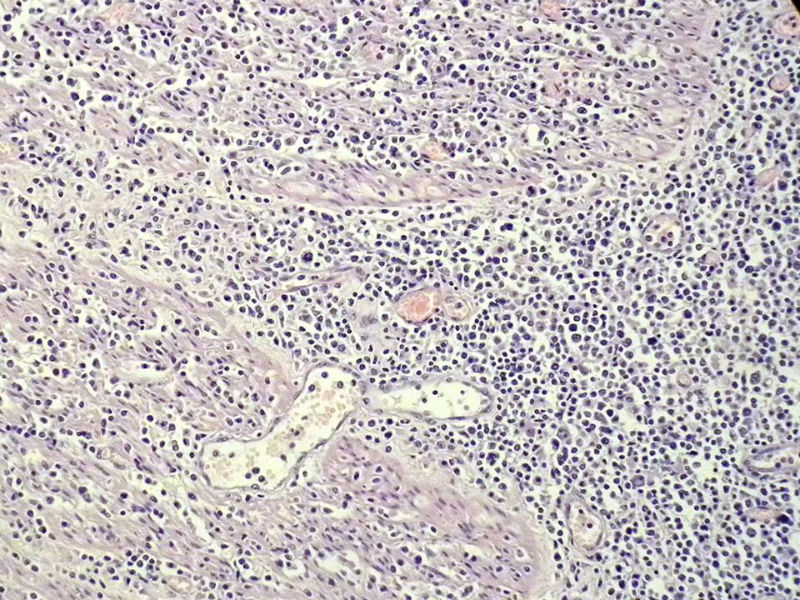

女,53岁,横结肠有9X6厘米大小溃疡,手术切除。

中老年人,溃疡很大,可见淋巴浆细胞样细胞弥漫浸润,散在大细胞,疑非霍奇颈淋巴瘤,倾向MALT伴浆样分化,不知是否破坏肌层?可否传肌层图?需IHC标记,鉴别淋巴瘤、腺癌及其它。

肉眼观仅是溃疡?有没有肠壁增厚、隆起?周围粘膜情况?肌层情况?有淋巴浆细胞样细胞、中心细胞,散在少量不成片的大细胞,不排除MALToma伴大细胞转化。

本例肉眼溃疡如溃疡性结肠炎,肠壁无明显增厚,表面辅以坏死,溃疡边缘稍隆起。镜下淋巴样细胞局限在粘膜层,肌层未见。谢谢!